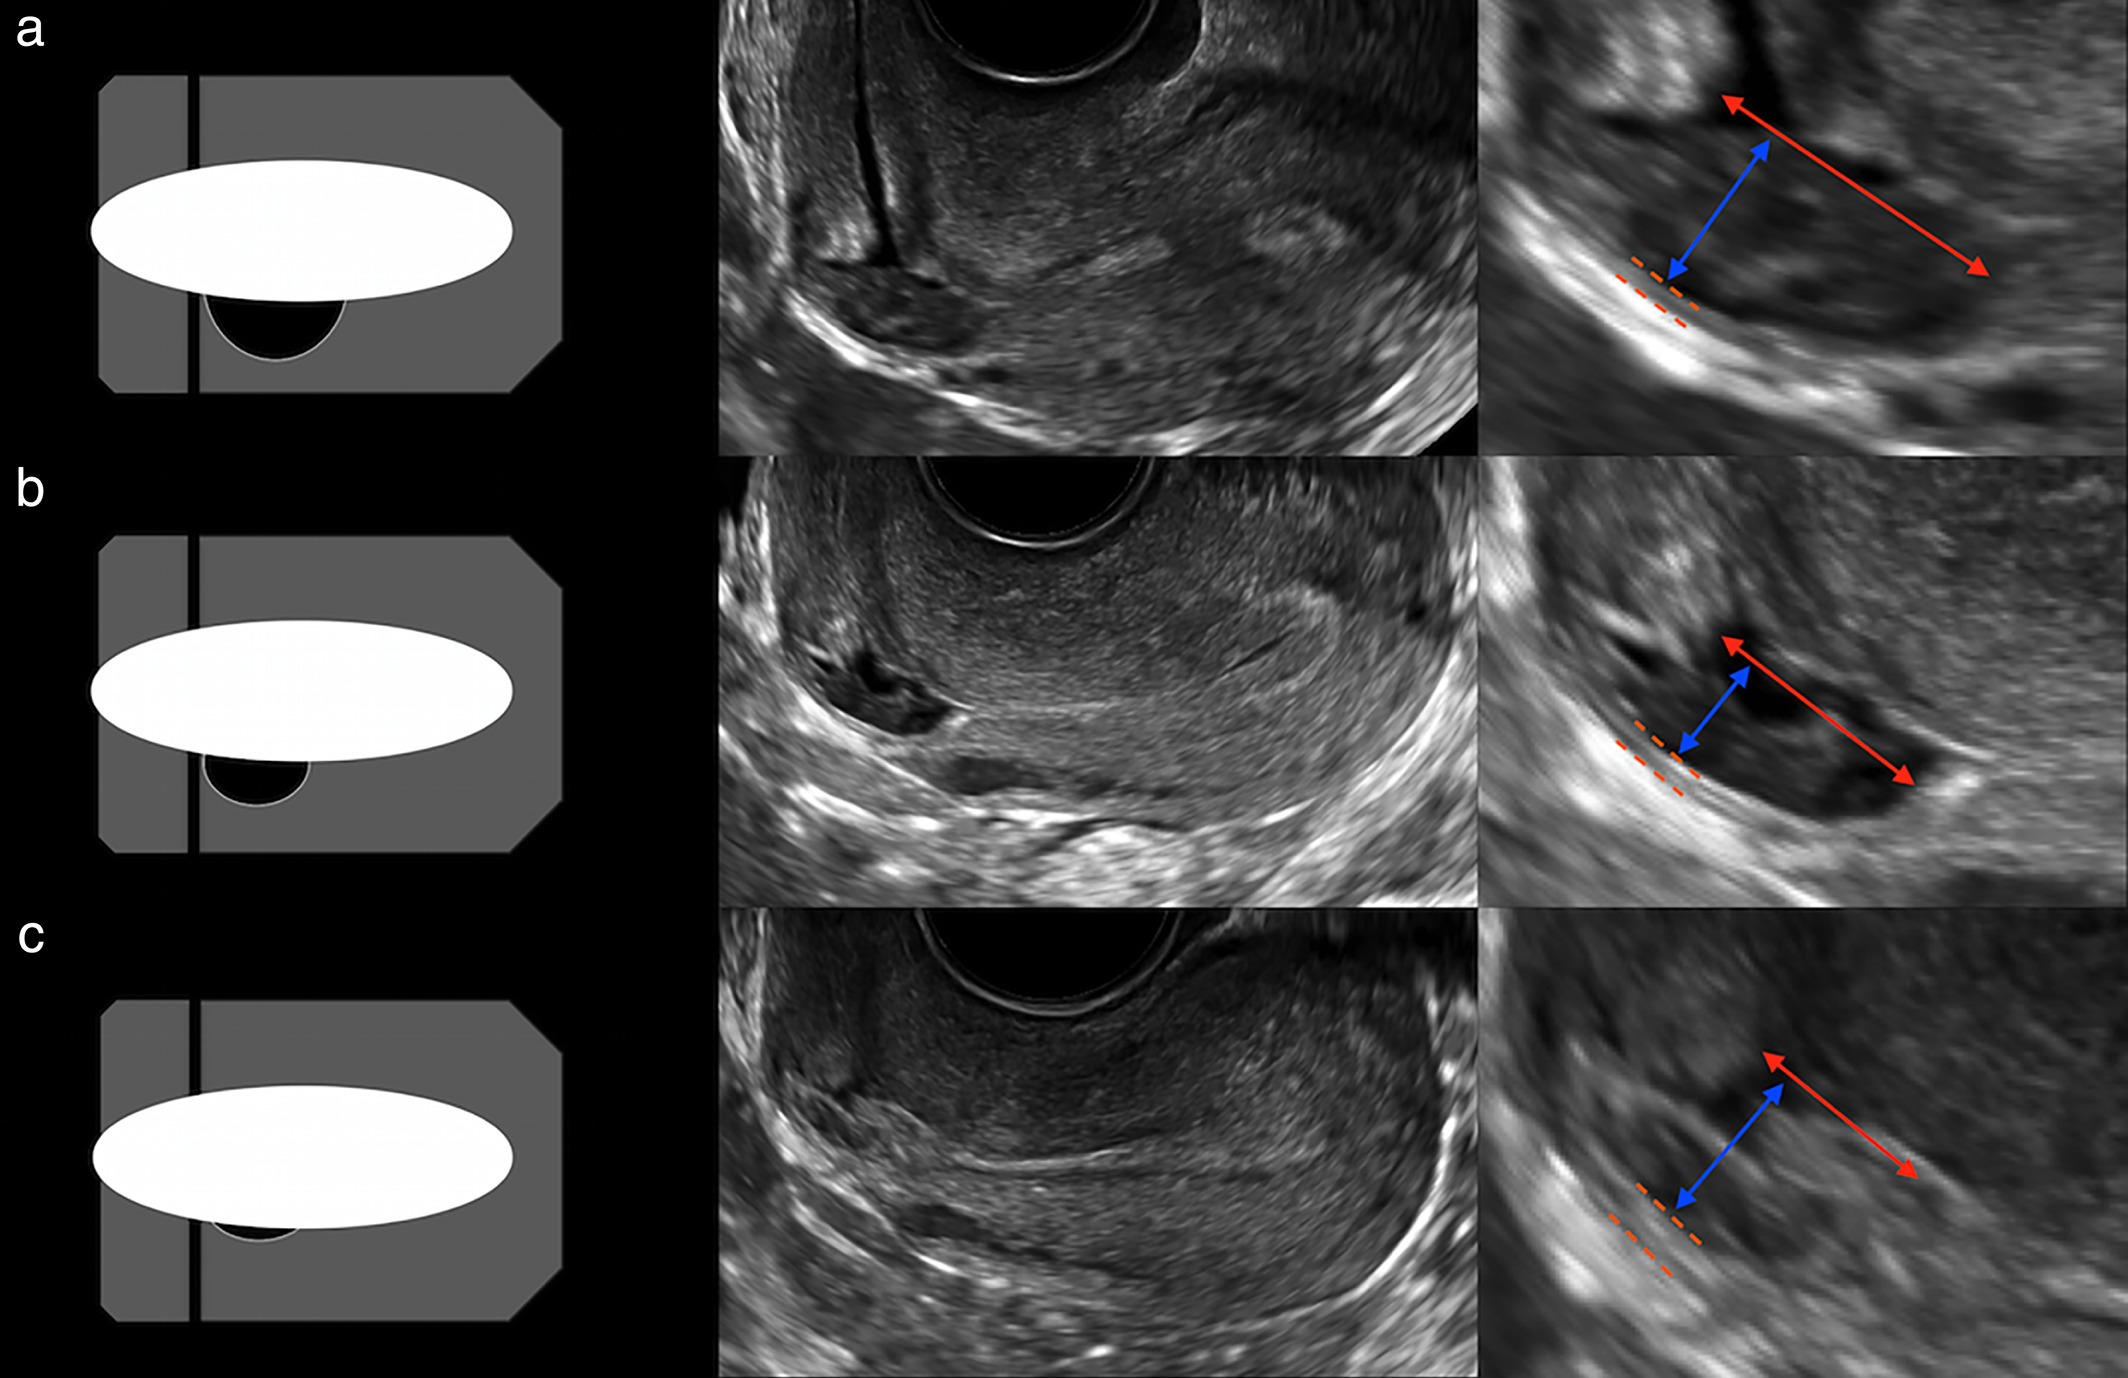

Correct measurements of uterine fundal internal indentation depth and angle: an important but overlooked issue for precise diagnosis of uterine anomalies

Congenital Uterine Malformation by Experts (CUME): better criteria for distinguishing between normal/arcuate and septate uterus?

Are the ESHRE/ESGE criteria of female genital anomalies for diagnosis of septate uterus appropriate?